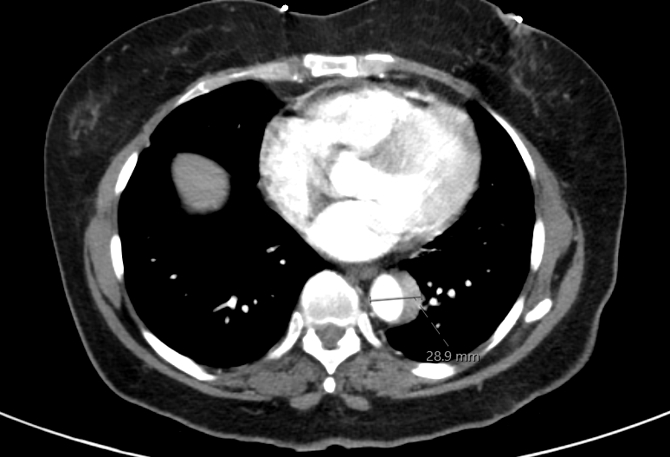

A 70-year-old woman with no cardiovascular history presented with sudden-onset, severe substernal chest pain radiating to the back while doing yard work, associated with diaphoresis, shortness of breath, and right-hand paresthesia. She was a never-smoker and denied alcohol or drug use. At urgent care, her blood pressure was 196/174 mmHg. After receiving aspirin and sublingual nitroglycerin, she was transferred to the ED with persistent back pain (BP 186/110 mmHg). D-dimer was 1.49. ECG showed no ischemia. CTA revealed a Stanford type B aortic dissection extending from the distal arch to the aortic hiatus. She was started on IV esmolol and nicardipine and transferred for vascular surgery evaluation. TTE showed normal LV ejection fraction (65–70%), grade 1 diastolic dysfunction, and moderate concentric LV hypertrophy. She was managed conservatively without surgery, transitioned to oral antihypertensives, and scheduled for surveillance follow-up to monitor for progression.

Initial labs showed elevated hemoglobin (18.2 g/dL) and hematocrit (58.9%), prompting outpatient evaluation. Hematologic workup revealed low erythropoietin (1.8 mIU/mL) and a positive JAK2 V617F mutation, confirming polycythemia vera. She was started on hydroxyurea, low-dose aspirin, and serial phlebotomy. Hematocrit and BP normalized, and repeat CTA at 3 months showed complete resolution of the dissection.